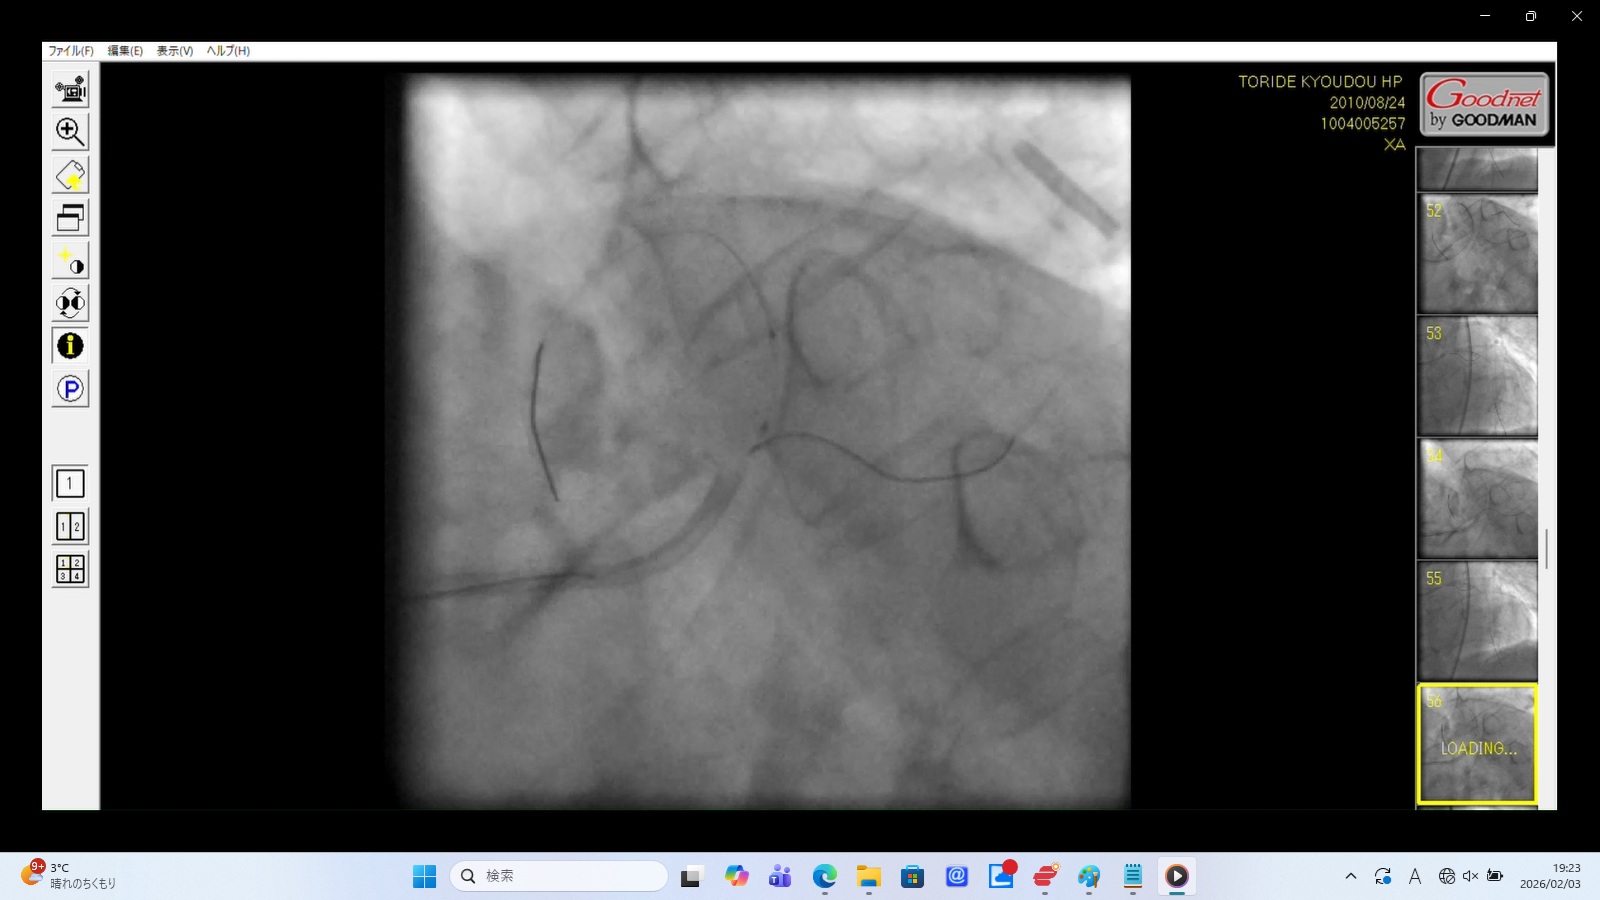

異物(人工物): 心臓の外側で拍動に合わせて浮遊する筒状の人工物(画像右上)

血管外に存在していることから、この人工物は血管を突き破って心臓の外に落下したものと考えられる。

形状からは人工物と考えられ、以下の可能性が考えられる。

・デリバリー中に脱落したステント

・カテーテルの先端チップがちぎれたもの

・ガイドワイヤーの断片

「医原性の異物遺残」であり、極めて重大な所見。

この人工物はそれなりのサイズがあり、これが血管外に脱落したことから、相当なサイズの血管穿孔があると考えられる。